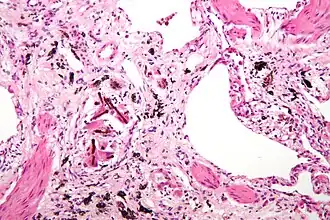

| Micrografia de de asbestose (com corpos ferruginosos), um tipo de pneumoconiose. H&E stain. | |